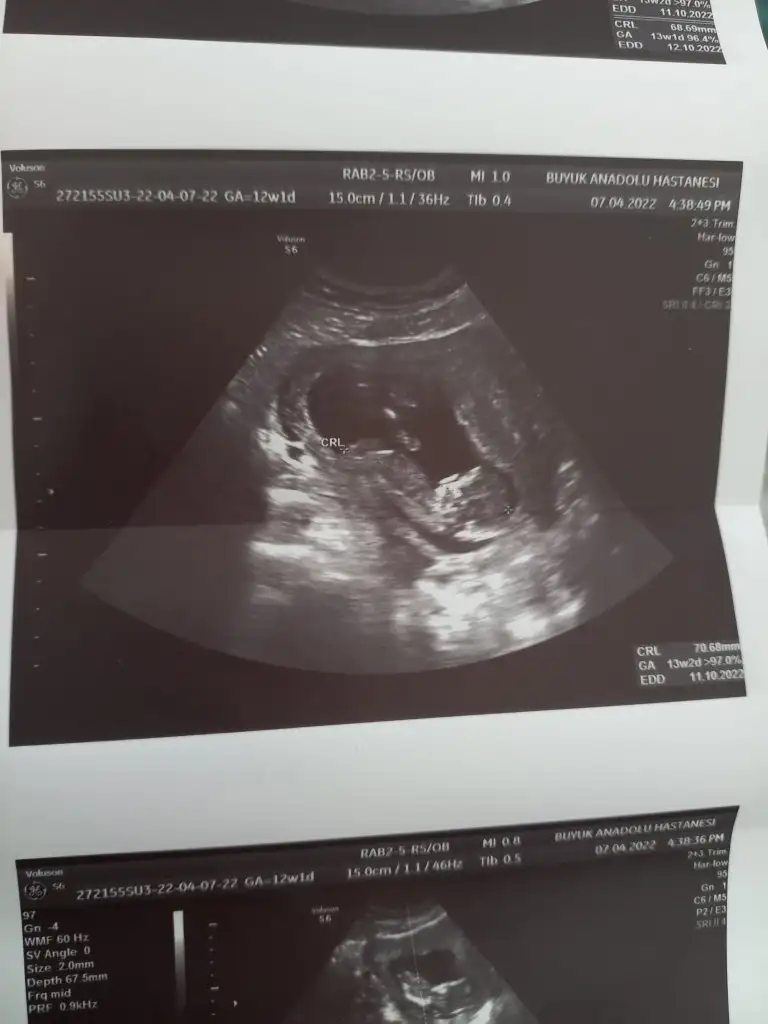

Kızlar doktordan çıktım. Şükürler olsun sağlıklı 😊 rahat rahat yatiyordu valla kolunu hareket ettiğini gordum. Keyfine diyecek yok:) 15 cmcik . Bu arada bugün 12+1 aslında ama 13 haftalik gözüküyor dedi. Yeni doktor olduğu için önceki ultrosonlara bakacak bakalim. Bu arda ihtimal bir cinsiyet söyledi tabiki 4ayliken dahakine cevap verecek

Eklentiler

• 16493405997085128056545747613441.webp

16493405997085128056545747613441.webp

23,6 KB · Görüntüleme: 65

• 16493406416935896458324250355155.webp

16493406416935896458324250355155.webp

22,5 KB · Görüntüleme: 67